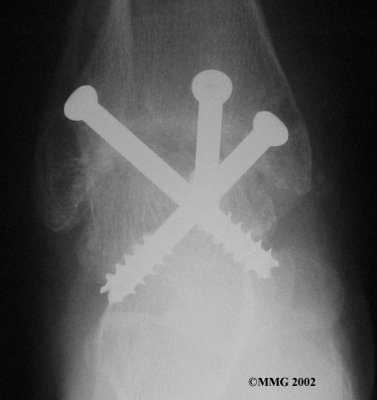

It is important when the surfaces are removed that the angles of the cut surfaces are correct. When the tibia is brought against the talus, the foot should be at a right angle to the lower leg. Once the cuts are made the bones must be held in place while they fuse. This can be done using large metal screws and metal plates if necessary. The screws are usually under the skin and are not removed unless they begin to rub and cause pain.

Inserting the screws

After ankle fusion, the physical therapists at FYZICAL Fort Myers Metro can help you learn to walk smoothly and without a limp. Although time needed for recovery varies among patients, an ankle brace will typically replace your cast after eight to 12 weeks. Your surgeon will take X-rays frequently to see if the bones are fusing together. You will probably need to use crutches during the time you wear the cast. As the fusion grows stronger, you will begin to put more weight on your foot when walking.